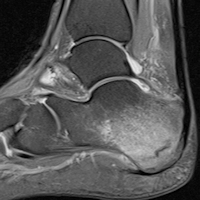

More complex questions require more advanced imaging, such as musculoskeletal MRI, Batlle said. Only a small number of stadiums have MRI scanners onsite, so players are typically sent on Monday to the same imaging facilities used by regular patients.

What sort of pathologies do radiologists working with the NFL see? Many of the injuries are similar to the sorts of musculoskeletal issues found in a typical weekend warrior, but with subtle differences.

For example, hamstring injuries are very common, Young said, with small tears constituting a sizable component of the MRI cases that are sent to University Hospitals. Maurer of the Cowboys also cited hamstring tears as a condition where MRI gives important details about the significance of the injury -- which can affect the duration of an athlete's recovery.

In addition, Young said he was surprised by how many post-traumatic and degenerative injuries are already present in athletes. This can make the diagnosis of acute injuries more challenging.

What's driving the growing role of radiology in sports medicine? The radiologists interviewed by AuntMinnie.com agreed that it's due in large measure to the growing power of MRI to shed light on injuries that were invisible on other modalities, particularly plain radiography.

"I think that public awareness of sports medicine injuries has definitely gone up with the advent of MRI," he said. "When I was child watching football in the '80s and '90s, no one would have heard of a partial tear of an MCL [medial collateral ligament], but now that is routine discussion on ESPN and how many weeks it might cause a player to be out."